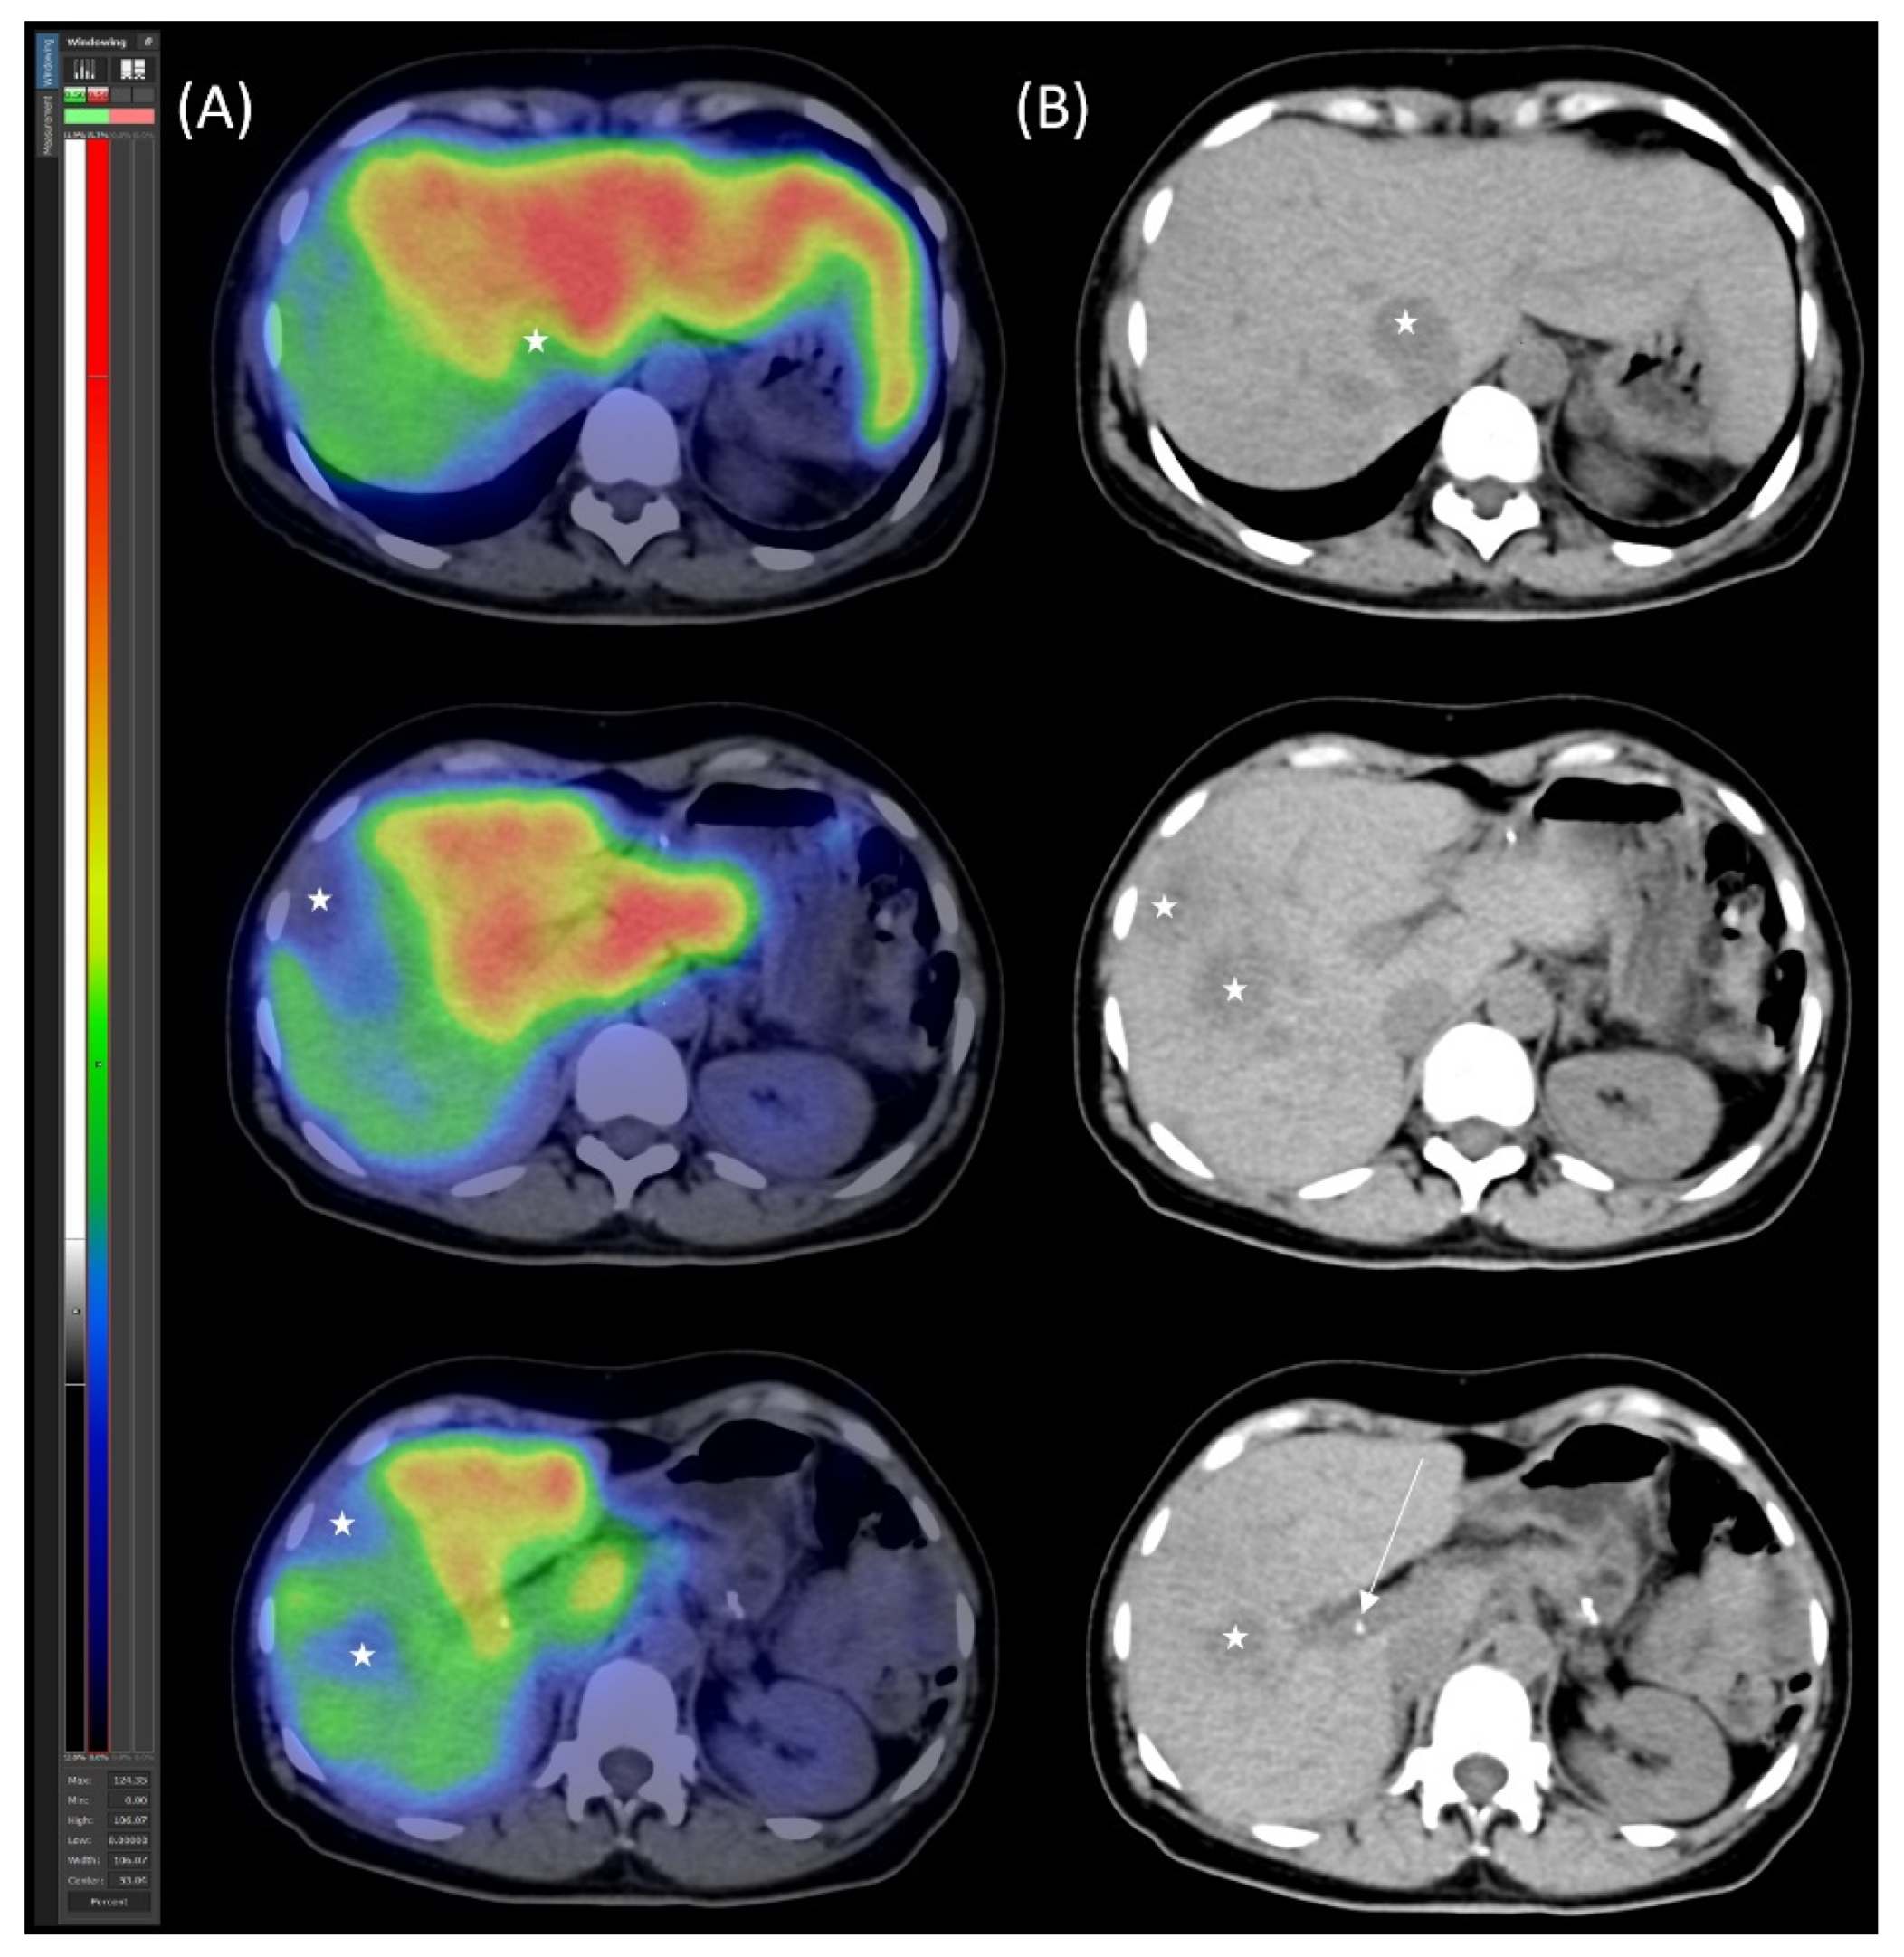

2.3. Preoperative Planning and Second-Stage Surgery